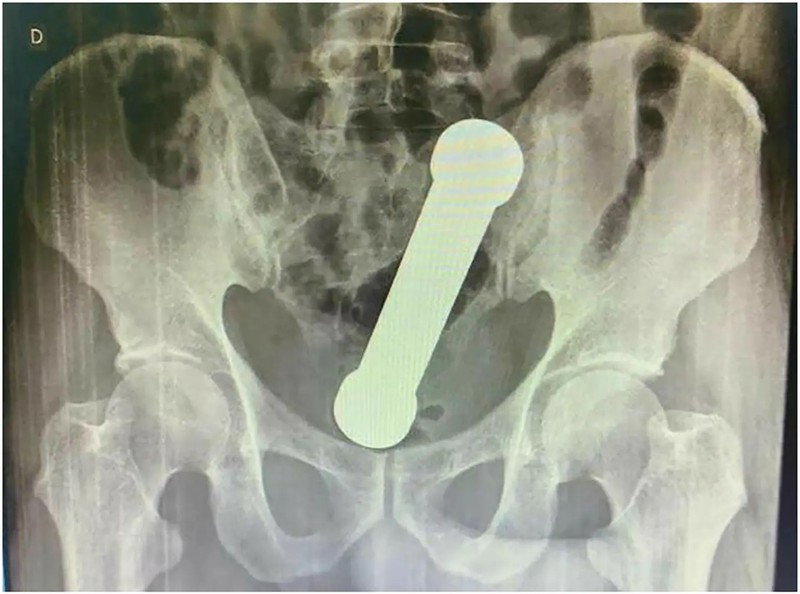

Seorang pria di Brasil mengeluh sakit perut setelah barbel nyangkut di anusnya selama dua hari. (Foto: International Journal of Surgery Case Reports)